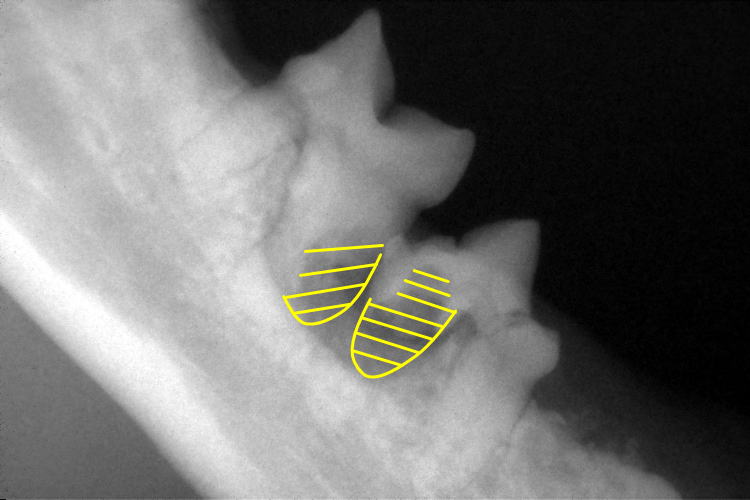

歯科レントゲン

右下顎臼歯のレントゲンです。

破歯細胞性吸収病巣により、歯根の一部が溶けていることが確認できます。(黄色斜線部分)

左下顎第1後臼歯も破歯細胞性吸収病巣により歯冠と歯根の一部が溶けていました。(歯色斜線部分)